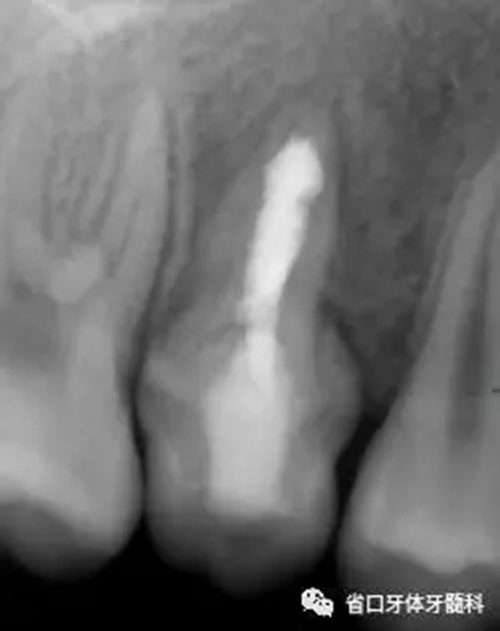

圖5 根管內(nèi)封vitapex

檢查:15臨時(shí)充填物完好,叩-,松-,牙齦未見明顯異常 ,X片示根尖低密度影消失,牙槽骨組織修復(fù),牙周膜連續(xù)

治療:15橡皮障隔離下,去除原充填物,顯微鏡下,清理根管內(nèi)糊劑,熱牙膠聯(lián)合iroot封閉劑垂直加壓充填,術(shù)后拍片,樹脂充填。

圖6 根管充填后